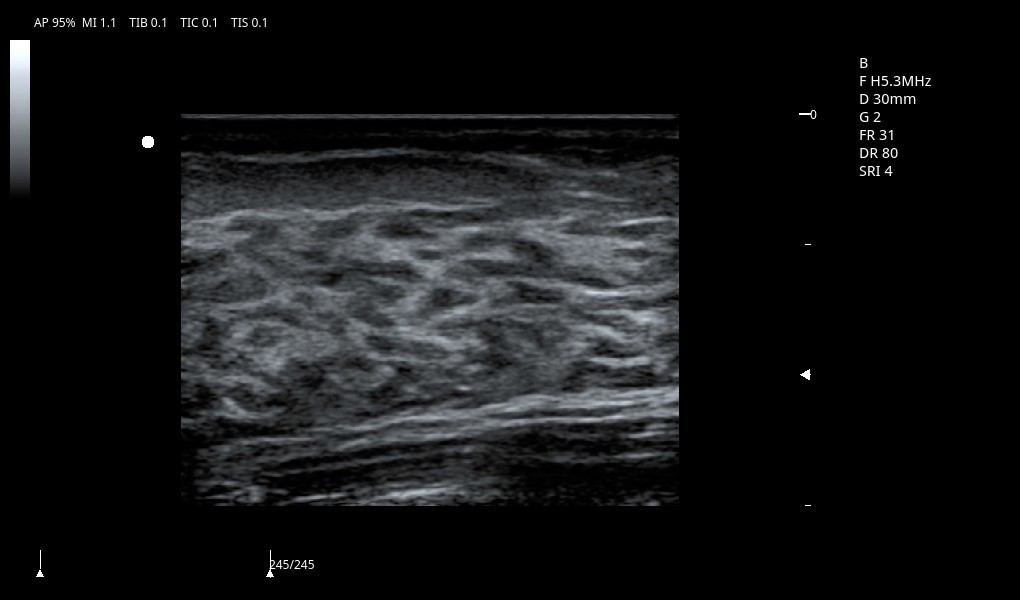

Excelentes imágenes clínicas

|

|

|

|

|

|